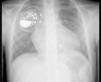

Doente do sexo feminino, de sete anos, com diagnóstico de transposição das grandes artérias com comunicação interventricular e estenose pulmonar. Submetida a construção de anastomose de Blalock Taussig modificada no período neonatal e cirurgia de Rastelli aos seis anos de idade. Verificado bloqueio auriculoventricular completo não reversível no período pós-operatório com necessidade de implantação de pacemaker VVIR (Microny II SR, St. Jude Medical, electrocateter de fixação passiva ISOFLEX). Um ano após correcção cirúrgica, recorreu ao Serviço de Urgência por estimulação peitoral pelo pacemaker. Na interrogação do pacemaker, verificada alteração do limiar de estimulação ventricular (variável e superior a 2,4V, sem alteração do valor de impedância e de sensibilidade). Nesta altura a paciente apresentava ritmo próprio de bloqueio auriculoventricular avançado. Realizada revisão cirúrgica com extracção do sistema por tracção manual do electrocateter que decorreu sem complicações. A análise macroscópica não evidenciou alteração aparente da integridade do electrocateter. Implantado novo sistema de pacemaker VDR (Identity VDR, St. Jude Medical, electrocateter AV Plus Dx, fixação passiva), através da veia subclávia direita. A onda P e onda R apresentavam amplitude de 2mV e 7,1mV respectivamente, com limiar ventricular de 0,75V. Imagem final mostrou sonda bem colocada, como evidencia Figura 1.

Ao 5.° mês verificado sensing auricular inadequado (< 0,1mV), com parâmetros ventriculares estáveis. Radiografia torácica mostrou repuxamento de sonda, enrolada na bolsa de pacemaker, compatível com síndrome de twiddler (Figura 2).